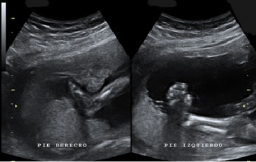

Ecografía de la semana 20

Primera gran "foto" del bebé, que examina todos sus órganos

Ecografía de la semana 20 o morfológica, así se denomina esta prueba diagnóstica, considerada como la primera "foto" del bebé. Decimos esto porque el ecografista recorre con mucha calma y cautela todas las estructuras básicas y órganos del bebé, que a esta edad gestacional se suelen ver con claridad. El pequeño aún se mueve con soltura dentro del líquido amniótico, a veces esquivando la mirada del ecografista, algo que en pocas semanas hará con mucha más dificultad. Merece la pena ver esta galería de ecografías de la semana 20 (y alrededores, puesto que se puede hacer a partir de las semana 18) en 2D, 3D y 4D. En la eco de la semana 20 también pueden detectarse algunas malformaciones fetales, pero lo usual que que se compruebe la buena salud del feto.